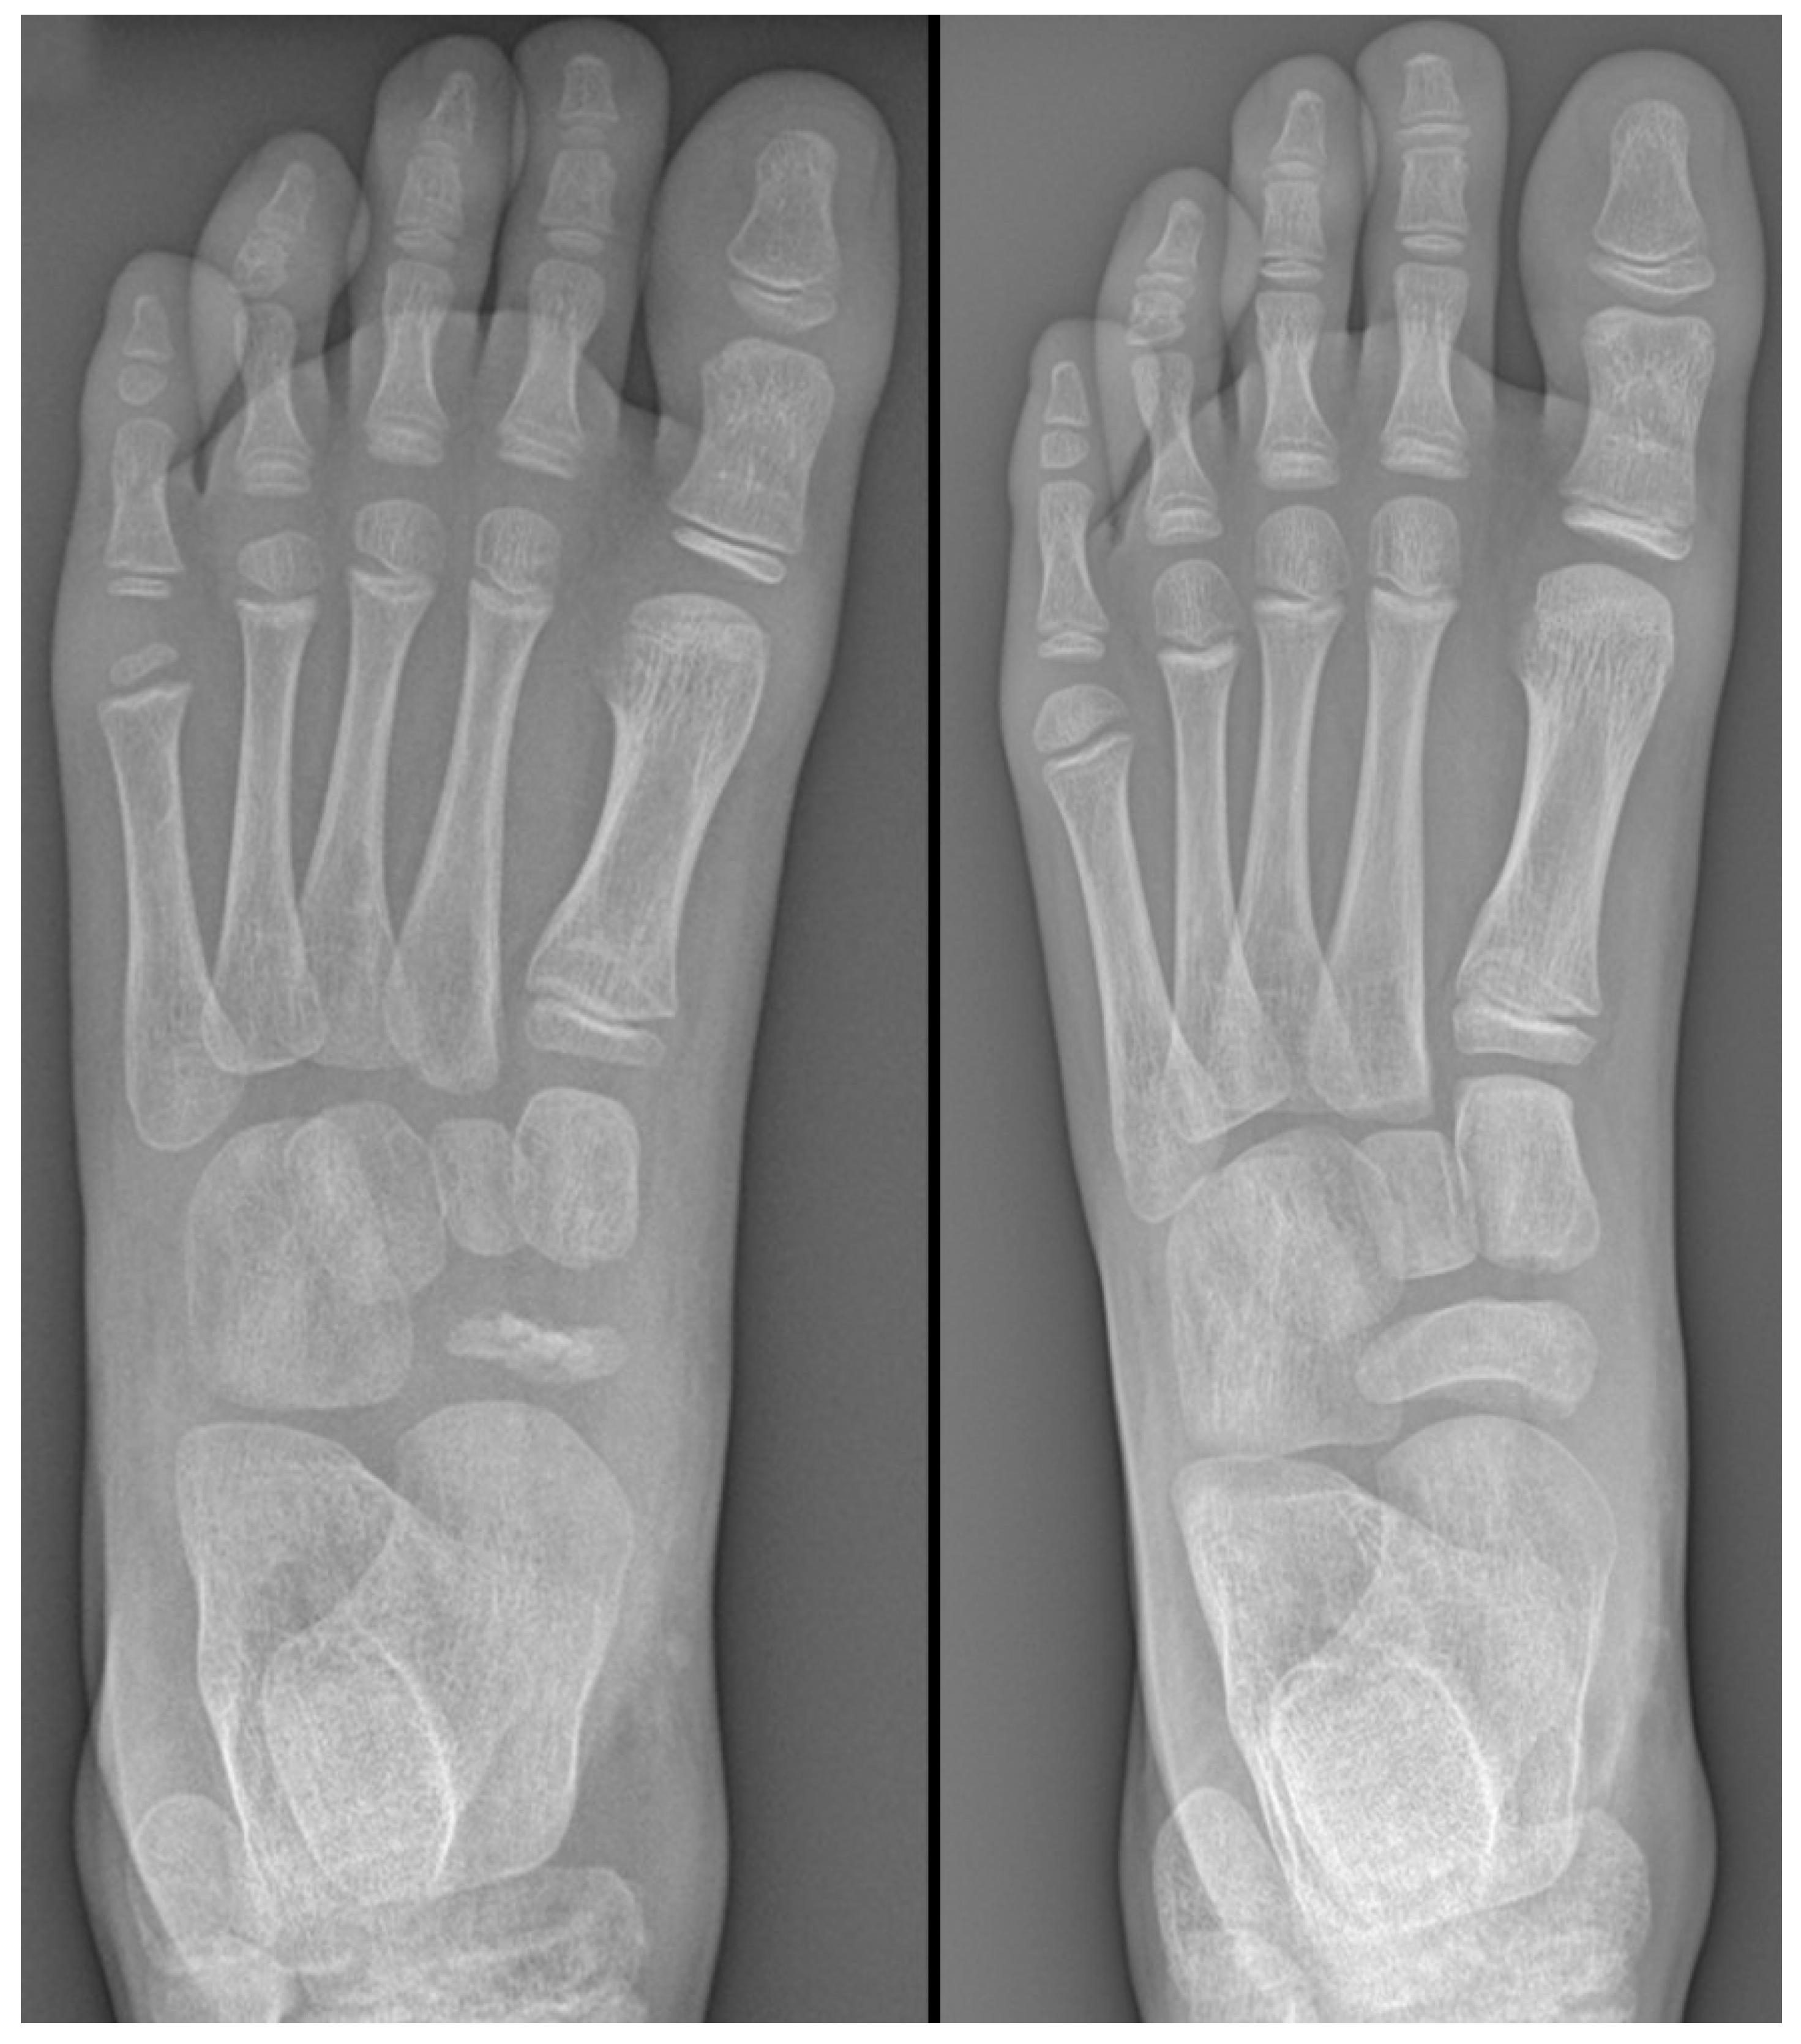

Plain radiographs are the cornerstone of imaging in the diagnosis of lesser metatarsal osteochondrosis. In the early stages of the disease, when supported by a suggestive clinical presentation, obtaining a comparative radiograph of the contralateral foot can be a useful diagnostic tool (Figure 9).

Figure 9.

Radiograph of a symptomatic 10-year-old female patient showing early sclerosis and flattening of the second metatarsal head on the left foot, compared to the contralateral side.

In the later stages, radiographs may reveal characteristic changes including subchondral sclerosis, fragmentation, and flattening of the affected metatarsal head (Figure 10 and Figure 11). In some cases, the presence of joint space narrowing or bony irregularities may also be observed. However, early changes, such as bone marrow edema or subtle cartilage damage, may not be visible on standard radiographs. MRI is particularly useful in the early stages of the disease, as it can detect bone marrow edema, which is a sign of active bone inflammation and necrosis, even before structural changes become apparent on radiographs (Figure 10, Figure 11 and Figure 12).